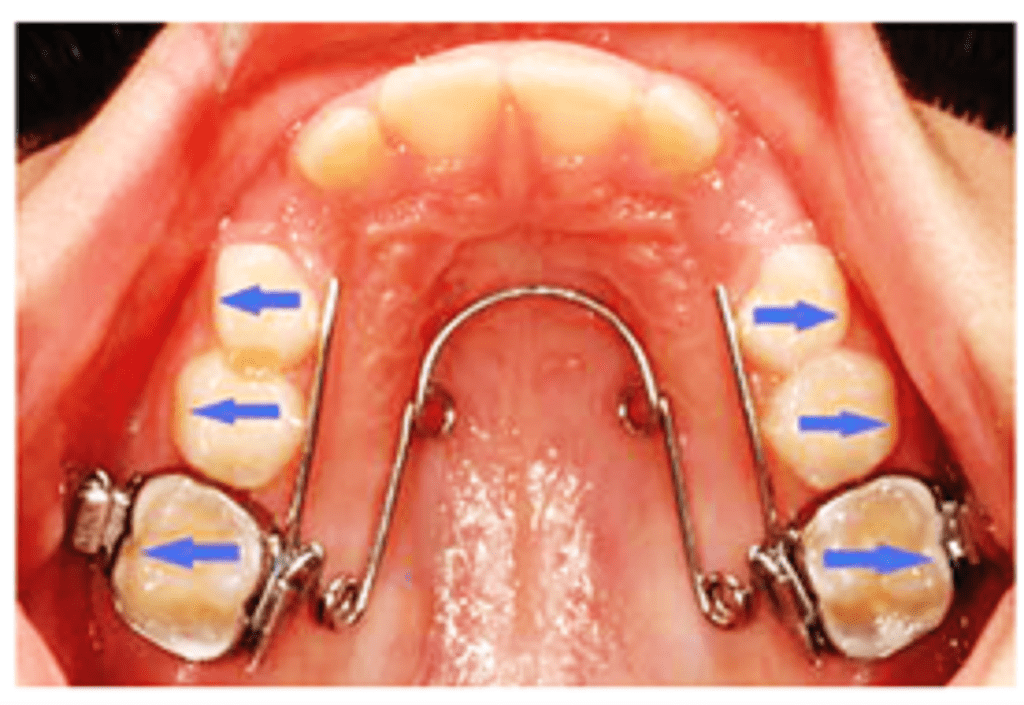

Quad/ Tri/Bi Helix appliance

Quad helix was introduced by Robert M Ricketts.

The appliance is a precursor to the tri- and the bi-helix appliances. They are all named after the number of helices incorporated in the appliance.

Appliance framework ̶ The quad helix consists of four helices made of 0.038″ diameter wire (elgiloy or stainless steel wire), soldered to the molar bands. The length of wire increases the range of action and flexibility, and decreases the force levels. The tri- and the bi-helix appliances incorporate only three and two helices respectively.

It is a fixed appliance comprising stainless steel bands cemented onto the maxillary first molars and a standard stainless steel arch attached to the palatal surfaces of the teeth.

Parts of quad helix: (A) posterior helix, (B) palatal bridge, (C) anterior helix, (D) anterior bridge and (E) outer arm.

The quad-helix consists of two anterior and two posterior helices. The portion of wire in between the two anterior helices is called the anterior bridge and that connecting the anterior helices and the posterior helices is called the palatal bridge. The free ends that are usually adapted close to the premolar teeth are called the outer arms. The outer arms are soldered to the molar bands. The posterior helix should not extend more than 2 mm distal to the first permanent molar.

Activation – The appliance is capable of producing differential expansion i.e. it can be activated to produce expansion levels in the premolar and molar regions.

It can be activated prior to cementation of the bands by stretching the molar bands apart or in the mouth with the use of three-prong pliers.

- In the anterior bridge: Results in expansion in the molar region

- In the palatal bridge: Derotation and expansion of molar on the same side and distalization of molar on the opposite side

- Outer arms are activated to expand canines and premolars

- Opening of posterior helix expands the buccal arm

An initial expansion of 8 mm will produce 14 oz of force. Average force is 200–400 g depending upon the amount of expansion or activation. The expansion of the steel arch (normally 10 mm before insertion) exerts a lateral force on the teeth, resulting in a predominant transverse dentoalveolar expansion of the maxillary arch. If necessary, the appliance can be reactivated after 6 weeks. Once inserted, the appliance is not dependent on patient compliance.